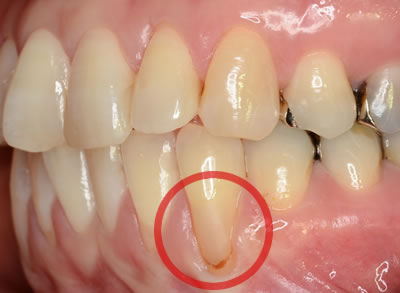

■治療前

歯列不正や、歯軋り・強すぎるブラッシング圧で歯肉が退縮してしまう事があります。特に前歯部においての歯肉退縮は、“審美的に大きな問題”となります。

その対処法として、結合組織を用いた『根面被覆術』があります。